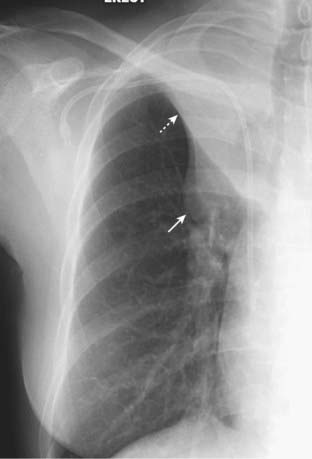

Figure 5-5 Left upper lobe atelectasis.

On the frontal projection (A), there is a hazy density surrounding the left hilum (solid white arrow) and there is a soft tissue mass in the left hilum (solid black arrow). Notice how the left hemidiaphragm has been pulled up to the same level as the right. The lateral projection (B) shows a bandlike zone of increased density (solid white arrows) representing the atelectatic left upper lobe sharply demarcated by the major fissure, which has been pulled anteriorly. The patient had a squamous cell carcinoma of the left upper lobe bronchus that was producing complete obstruction of that bronchus.

image Left upper lobe atelectasis (see Fig. 5-5)

On the frontal radiograph:

There is a hazy area of increased density around the left hilum.

There is a leftward shift of the trachea.

There may be elevation with “tenting” (peaking) of the left hemidiaphragm.

Compensatory overinflation of the lower lobe may cause the superior segment of the left lower lobe to extend to the apex of the thorax on the affected side.

On the lateral radiograph:

There is forward displacement of the major fissure, and the opacified upper lobe forms a band of increased density running roughly parallel to the sternum.